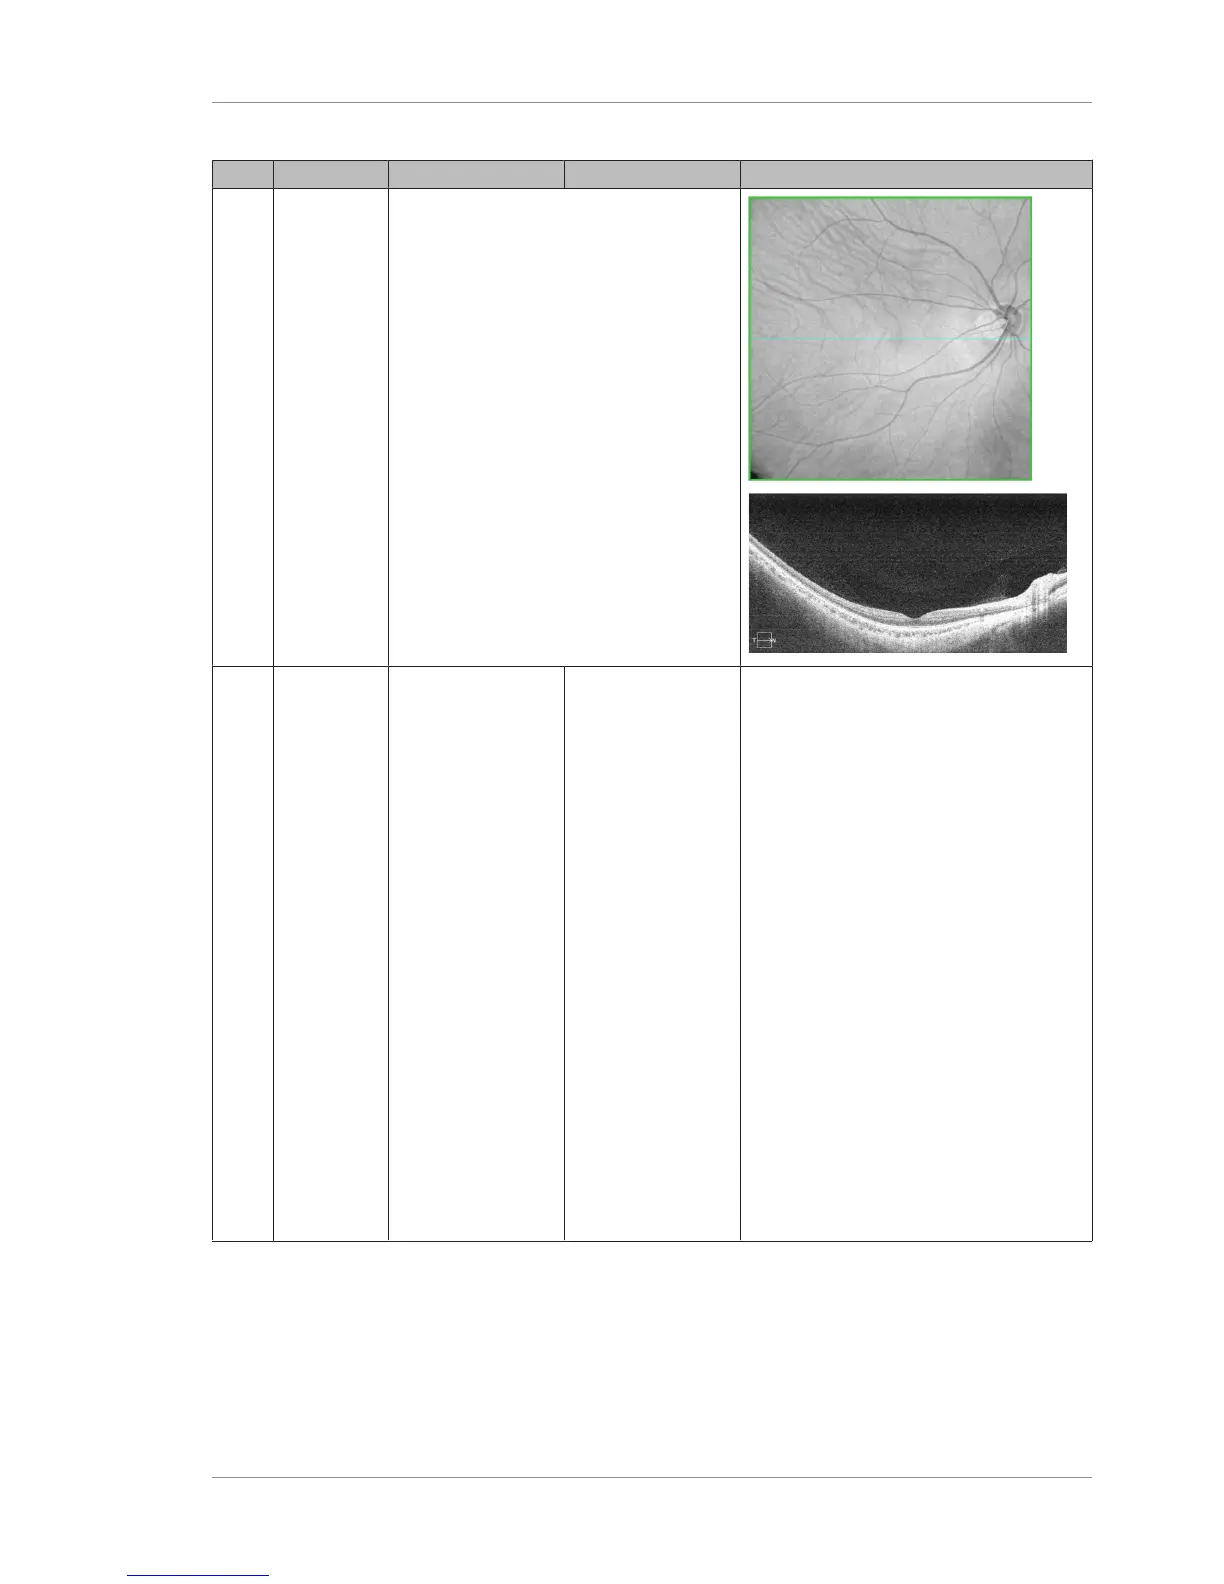

Pos Name Inner Boundary Outer Boundary Example

2 OCT Fundus

The struc-

tural view

of the

retina.